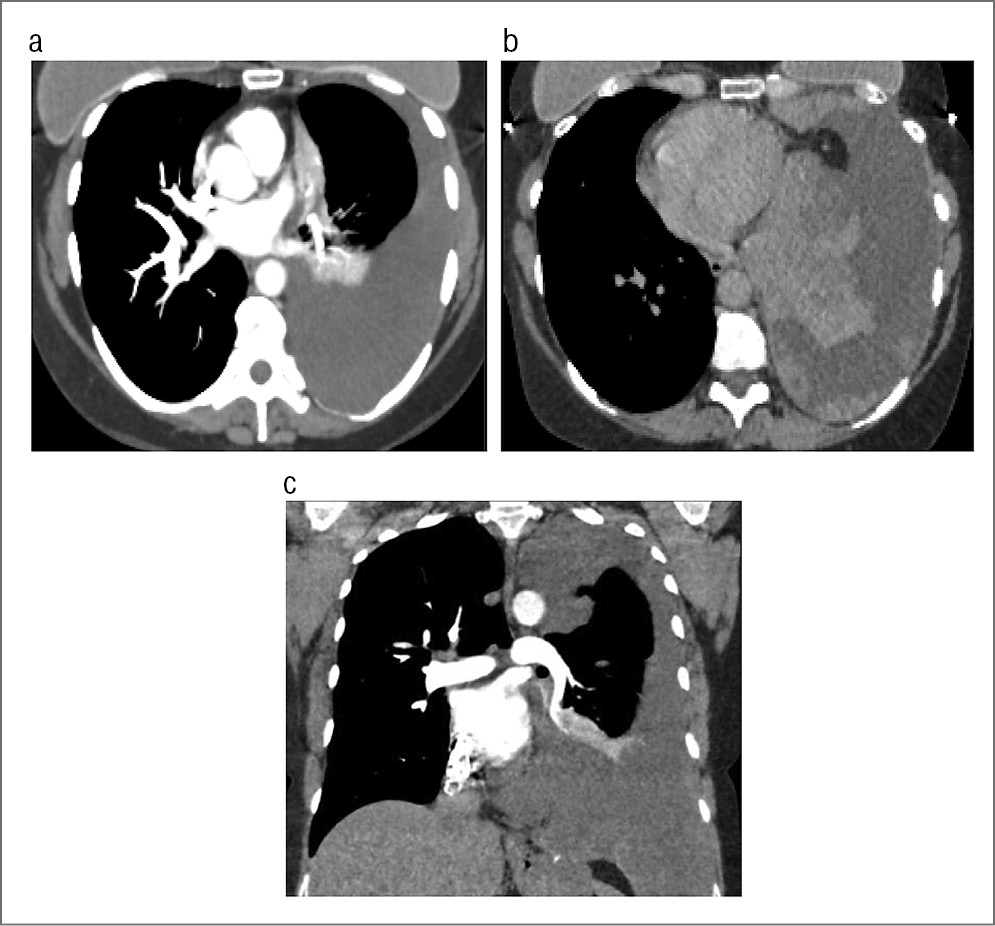

Пациент М., 77 лет. Диагноз: гигантское новообразование левого гемиторакса. Жалобы на чувство тяжести в левой половине грудной клетки, одышку при незначительной физической нагрузке, сухой кашель, потерю массы тела за последний год на 6 кг. Анамнез: со слов пациента известно, что в 1999 г. впервые при рентгенографии выявлено образование нижней доли левого легкого (данные обследования отсутствовали, характер и исходная локализация образования неизвестны). По этому поводу пациент регулярно не обследовался и у врача не наблюдался. В 2014 г. стала нарастать одышка. Поступил в отделение торакальной хирургии УКБ №1 для дообследования и оперативного лечения. При проведении МСКТ с контрастированием выявлено гигантское образование левого гемиторакса с гетерогенной структурой, неравномерно накапливающее контрастное вещество. Опухоль смещала вправо средостение, которое компримировало легочные сосуды без признаков инвазии. Перикард также интактен (рис. 9, a–c).

Рис. 9. МСКТ: а – аксиальная проекция; b, c – МПР во фронтальной и сагиттальной проекциях. Визуализируется гигантское образование левого гемиторакса неоднородной структуры, неравномерно накапливающее контрастное вещество.

Опираясь на данные обследования, преимущественно на результаты МСКТ, при котором не выявлено признаков опухолевой инвазии структур средостения, решено провести торакотомию слева. Однако установить исходную локализацию опухоли в силу ее огромных размеров не представилось возможным. Проведена операция по удалению гигантской опухоли диафрагмы (рис. 10, a–c) с краевой резекцией верхней доли левого легкого. При гистологическом исследовании: нейрофиброма.

Рис. 10. а – фото операции; b, c – опухолевый узел.